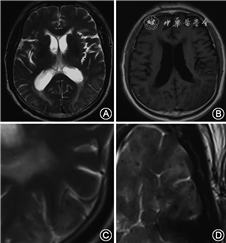

明显的脑微出血偶尔可在T2WI上看到(图2),但脑微出血的识别更多地依赖MRI梯度回波序列(gradient echo, GRE)或磁敏感加权序列(susceptibility weighted imaging, SWI)。微小血管病变导致血液外渗,在GRE或SWI序列上表现为2~5 mm大小的圆形低信号区(图1,3)。钙化、离子沉积、海绵状血管瘤等与脑微出血表现类似,应注意鉴别[28]。

扩大的PVS在MRI上可见,因此也常称为MRI可见的PVS,其信号特征与脑脊液类似,T2WI呈高信号、T1WI低信号,T2FLAIR示病灶周边无高信号,是与腔隙性梗死区别的关键[6, 28]。位置分布特征也是区分CAA和高血压性相关PVS的主要依据。前者主要位于半卵圆中心(图2),后者的PVS主要见于基底节区。半卵圆中心PVS的扩大可能提示Aβ清除系统的功能障碍,促进Aβ在脑膜和皮质表浅部位血管壁内沉积[42]。

尽管ICAA与CAA密切相关,但其临床特征显著不同于CAA。ICAA可分为CAA相关炎症(CAA related inflammation, CAA-ri)和Aβ相关血管炎(Aβ related angiitis, ABRA), 两者分别以血管周围炎性浸润和透壁性血管炎为病理特征。ICAA可发生于多个部位,仅有1/3累及枕叶[64, 65]。ICAA症状多样,以亚急性认知功能下降、癫痫和头痛最为常见[66]。ICAA通常为不对称的大片白质病变,影像学特点符合血管源性水肿的特征,可有占位效应、脑实质或脑膜强化(图4),与AD患者接受抗Aβ单克隆抗体治疗后出现的“Aβ相关影像异常(Aβ related imaging abnormality, ARIA)”类似,后者包括大片脑实质水肿、脑沟渗出和脑微出血[16, 65]。ICAA和ARIA可能具有类似的发病机制,针对血管壁内Aβ的免疫反应起到关键作用。在2篇个案报道中,ICAA和ABRA患者的脑脊液中均发现了针对Aβ的抗体[65]。相对于原发中枢神经系统血管炎,ABRA发病年龄相对较大、蛋白升高更为明显、较少发生梗死,出血发生率更高,脑膜强化更为常见,但均不具有特异性[67]。